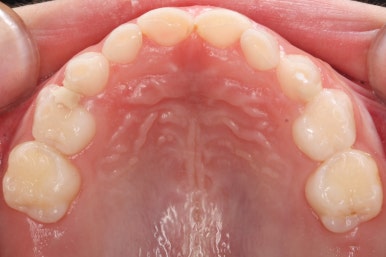

얼굴 모습입니다.

아래턱이 크다거나 하는 턱뼈의 문제점은 보이지 않았습니다.

만 6세 이후 검진이 중요한 또다른 이유는 이 시기에 골격의 문제가 발견된다면 "성장교정", 즉 턱뼈가 자라는 것을 양호하게 조절해 줄 수 있습니다.

만 6세 이후 검진 및 X-ray!! 다시 한 번 말씀드리지만, 반드시 필요합니다.